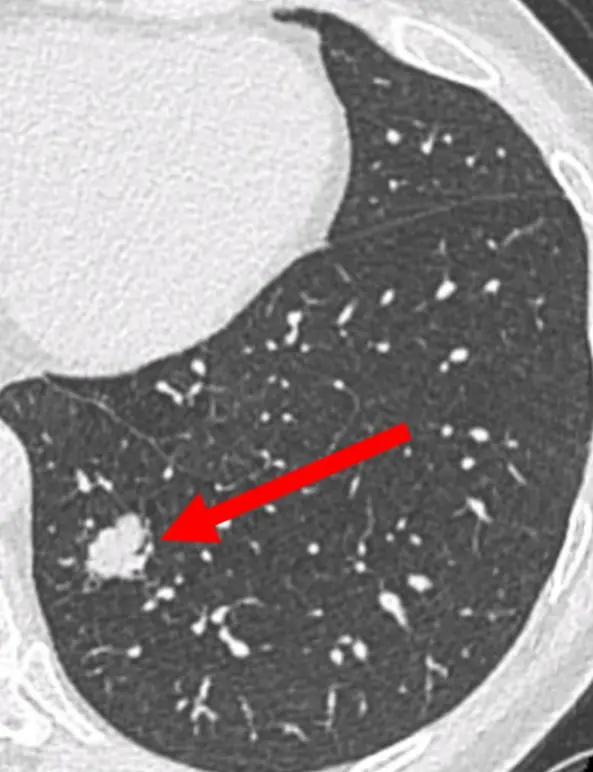

L’intelligence artificielle (IA) appliquée à l’imagerie thoracique dans le dépistage du cancer du poumon intervient à trois niveaux : i) l’aide à la détection de nodules, ii)la caractérisation de la probabilité de malignité du(es) nodule(s) détecté(s) et, iii) l’aide à la prédiction d’apparition du cancer.

Quinze pourcents des personnes qui font l’objet d’un dépistage du cancer du poumon se voient découvrir un nodule de nature indéterminée (NNI) sur le scanner de dépistage. Moins de 15% de ces NNI sont des cancers débutants. Devant un NNI deux attitudes sont proposées : simple surveillance radiologique (une stabilité oriente vers la nature non cancéreuse du NNI) ou abord diagnostique qui n’est pas aisé car il s’agit de toutes petites lésions situées en plein milieu du poumon. Une troisième attitude fait l’objet d’évaluation dans certains centres spécialisés c’est l’administration de traitement préventifs, encore appelée interception du cancer. Nous envisageons de combiner les deux dernières stratégies grâce aux possibilités de l’endoscopie robotisée qui permet la caractérisation histopathologique, immunologique et moléculaire de lésions inaccessibles par les techniques diagnostiques usuelles.